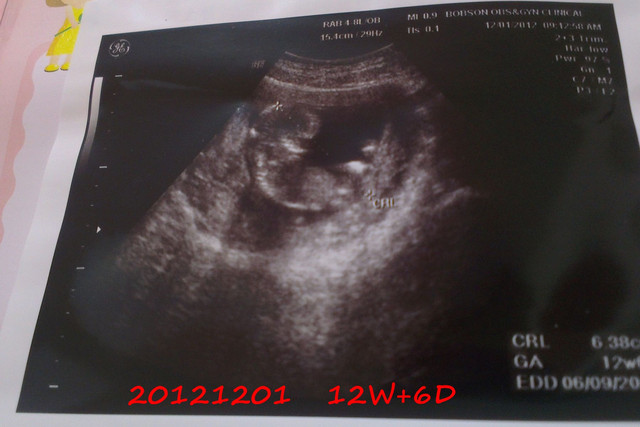

20121201去產檢的時候,發現小章魚已經成形囉

整個身體和頭都發展得很好

已經出現人的形狀了

感覺好特別

每天都在變化耶

而且這時已經滿3個月囉

終於過了安全期

而且這時的小章魚脊髓已經成形了

看看超音波照的好清楚

骨骼發育也很好